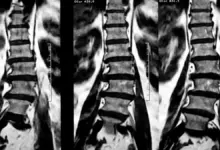

- Hérnia de disco: A hérnia de disco ocorre quando um dos discos intervertebrais da coluna vertebral se desloca e comprime as raízes nervosas, causando dor na região lombar e, às vezes, na perna.

- Estenose espinhal: Esse problema é caracterizado pelo estreitamento do canal espinhal, o que pode comprimir as raízes nervosas e causar dor na região lombar.

- Espondilolistese: A espondilolistese ocorre quando uma vértebra se desloca em relação à vértebra abaixo, causando dor na coluna lombar e instabilidade na região.